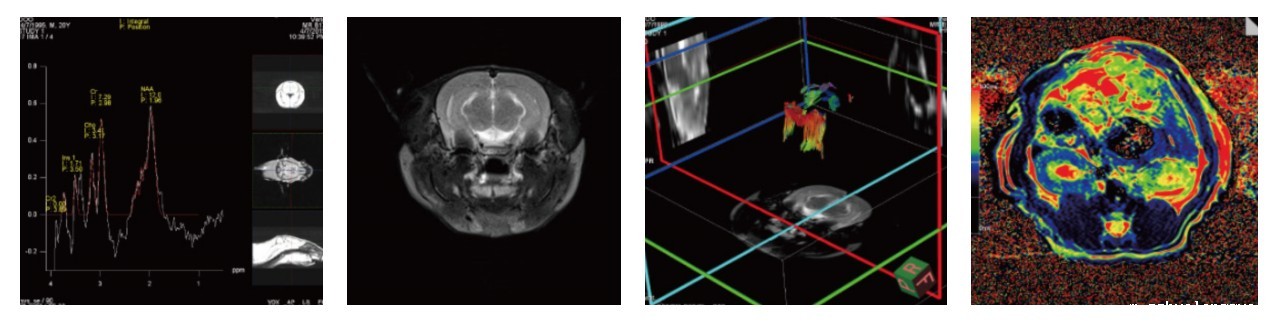

图2 结果展示

四、案例展示

(1)脑部核磁检测应用

图3 脑分数各向异性(FA)参数。(A)在海马上使用放大 (B)海马层三个分层:辐射层、分子层和分子层